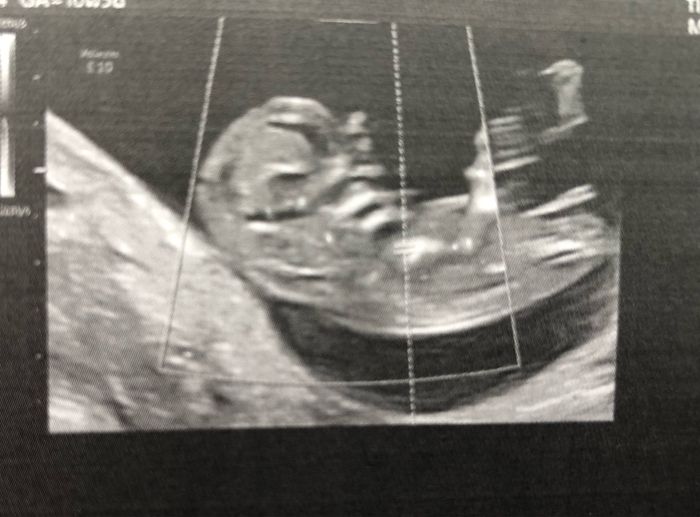

Ciao, ci provo anch’io per curiosità 😊Secondo voi si può già capire in qualche modo se femmina o maschio? Eco interna di ieri a 9 settimane.Grazie per chi vuol azzardare...